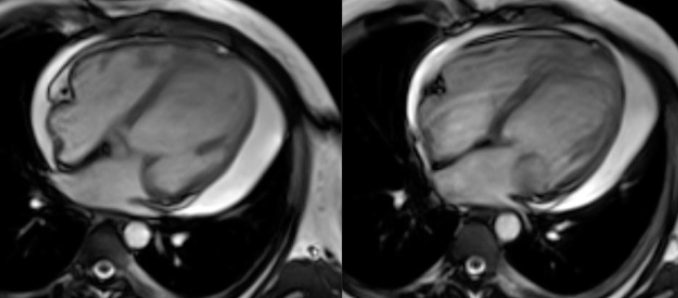

COD 077 - Decoding Septum Predominant Hypertrophic Cardiomyopathy

Understanding standard septum predominant HCM